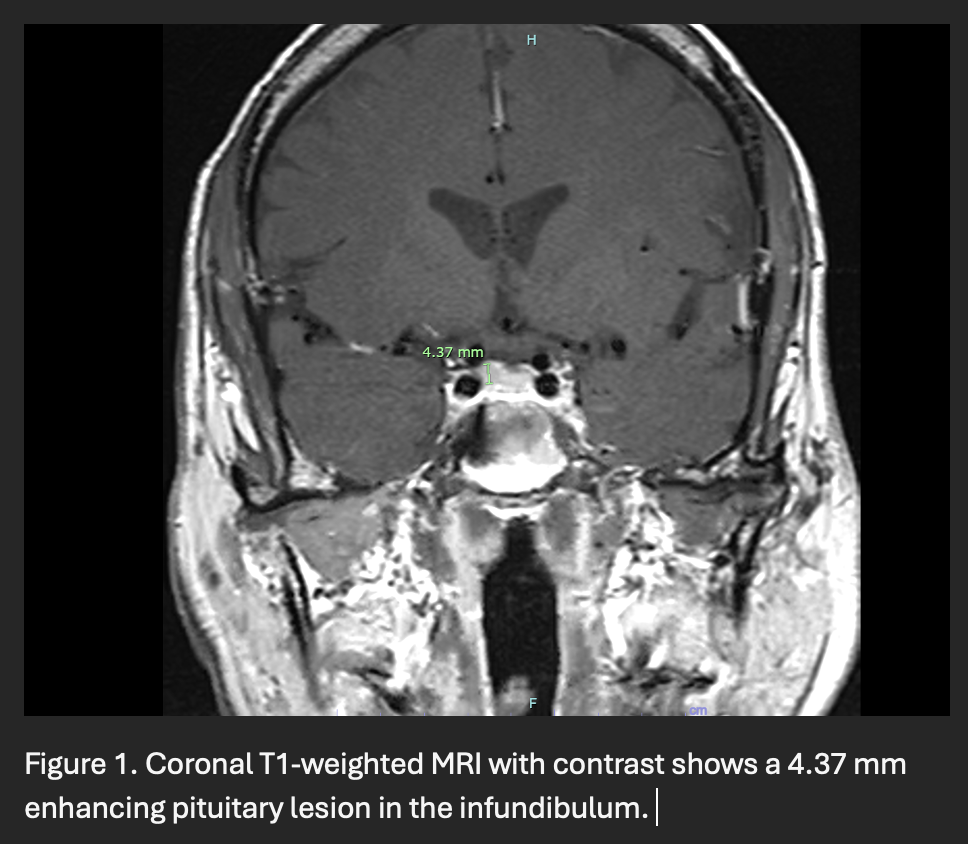

Results: A 60-year-old man presented with a year-long history of progressive ataxia, dysarthria, dysphagia, and fatigue. Three years prior, he developed diabetes insipidus due to a pituitary lesion [Figure 1], initially thought to be lymphocytic hypophysitis. Extensive ataxia workup, including autoimmune, paraneoplastic, genetic testing, FDG-PET, and DaT scan, was unremarkable. Three months later, jaw pain led to a biopsy-confirmed LCH diagnosis, retrospectively linking it to his pituitary lesion. Despite progressive cerebellar symptoms, brain MRI showed only nonspecific white matter hyperintensities, lacking characteristic ND-LCH findings [Figure 2]. He was treated with vemurafenib (480 mg BID), though dose reductions were required due to side effects. After 13 months, ataxia stabilized, but dysphagia and dysarthria worsened. A trial of high-dose methylprednisolone (1,000 mg daily for three days) provided no benefit.

Figure 1